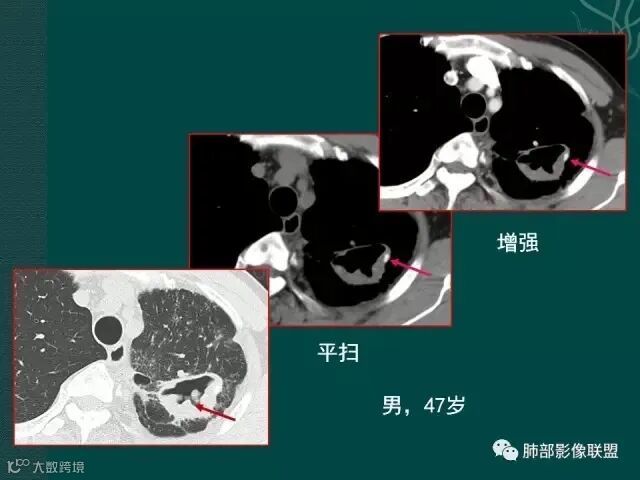

大片液化坏死,内多发空泡,初学者可能感觉是感染,但红箭头所指洞壁虽然不很厚,但仍可见到边界不清的低密度区,黄箭头所指病变侵犯胸膜。

上一个是磨玻璃密度肺癌,边缘清晰,内有分隔,空洞型肺癌伴磨玻璃密度影的,100%为腺癌,很显然这是个假性空洞;

下一个也是肺癌,内有分隔,外下缘箭头所示也是磨玻璃影,这也是腺癌,同时可见叶间裂有转移灶。